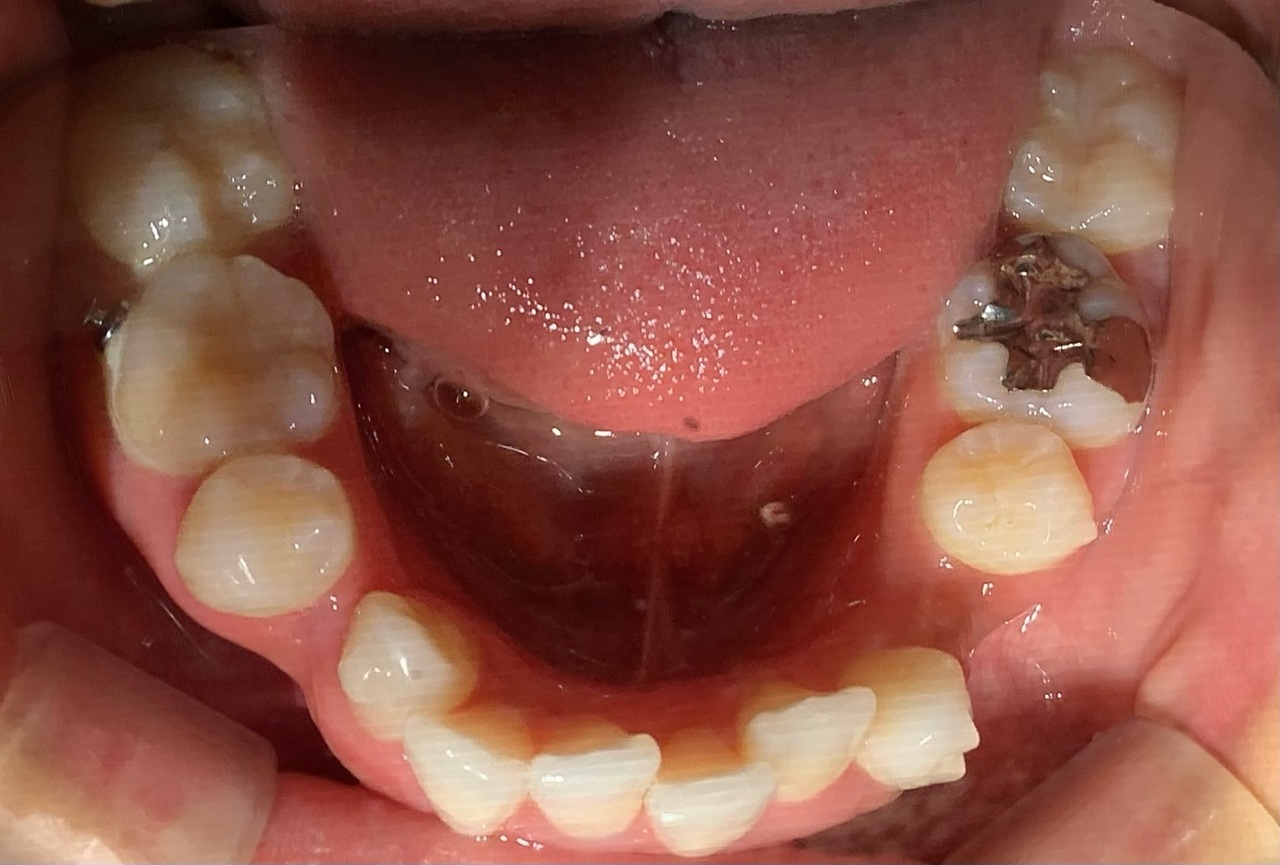

3か月前の写真と比較してみると、上下共に大きな変化が見られるようになってきました。

一つは、2本の八重歯が下に下がり、隣の歯と並んでいるのが分かります。おかげで現在は、ブラッシングがしやすくなり、毎日の歯磨きのストレスが無くなりました。

二つ目は、下の歯がすごくガタガタになっていましたが、現在は、綺麗に並んでいるのが分かります。

9か月が経ち、歯並びの変化があるとともに、噛み合わせが少し違和感に感じることがありますが、引き続きマウスピース装置を付け、様子を見ていきたいと思います。 次回のブログもお楽しみに!★(^^♪

矯正開始9か月後